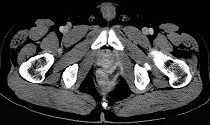

- 单项选择题男,28岁, 高热,肛门坠胀, 频有便意,直肠指诊时触及直肠粘膜下饱满, 柔软,压痛的肿块, CT检查如图,诊断为 ( )